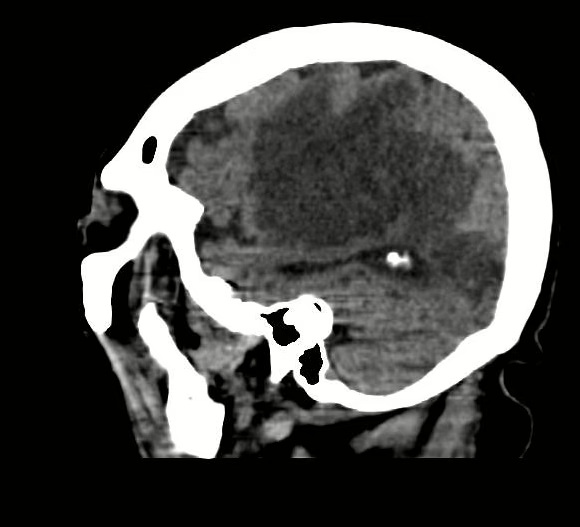

Estructuras óseas, sin evidencia de lesiones líticas, blásticas o perdida de la contigüidad. Se consigna hiperostosis frontal. Llama la atención concavidad de hueso frontal de lado izquierdo en áreas de hiperostosis que presenta una base de 13.5 X 11.2 mm, con concavidad de 6.6 mm.

Hoz cerebral, con calcificaciones hacia la convexidad.

Sustancia gris y blanca, hacia lóbulo frontal, parietal y temporal izquierdos, con área hipodensa, irregular, bien definida, que mide 6.21 X9.27X 4.27 cm, en su eje longitudinal, anteroposterior y trasversal respectivamente, con leve efecto de masa hacia ventrículo lateral izquierdo. A nivel de lóbulo insular derecho, con pequeña área ovoidea, regular, bien definida, isodensa a líquido cefalorraquídeo, que mide 13.7 X 8.9 mm. Resto con adecuada diferenciación.

Silla turca, se observa vacía.

APARENTE MENINGIOMA CALCIFICADO A NIVEL FRONTAL IZQUIERDO.

HIPEROSTOSIS FRONTAL.

ARACNOIDOCELE SELAR GRADO IV.